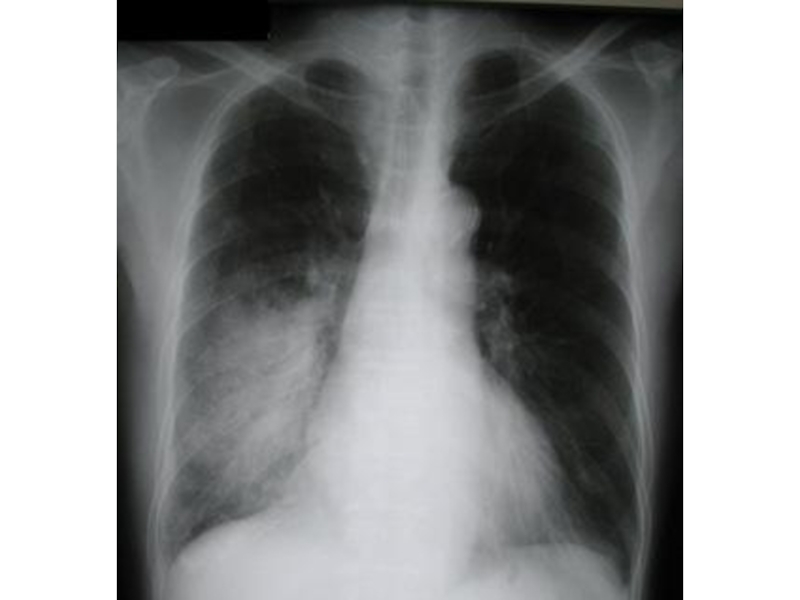

Крупозная пневмония (процесс захватывает целую долю, иногда все легкое, сопровождается воспалением

плевры):

На стадии прилива (первые 2-3 дня болезни альвеолы расширены и заполняются экссудатом) воздушность легочной ткани несколько снижена, легочный рисунок усилен, корень легкого расширен на стороне поражения.

На стадии опеченения (длится 3-5 дней, в альвеолах откладывается фибрин, в экссудат проникают клетки крови — сначала эритроциты, затем лейкоциты) воздушность резко снижена, корень легкого на стороне патологии расширен, прилежащая плевра утолщена, в плевральной полости может определяться экссудат. На снимке видна интенсивная тень в проекции одной или нескольких долей.

На стадии разрешения (наступает обычно к 7-10-му дню болезни) легочный рисунок усилен, корень легкого расширен, тень уменьшена и фрагментирована.

Обогащение легочного рисунка и расширение корня легкого сохраняется еще на протяжении месяца после исчезновения клинических проявлений.

а — красное опеченение; б — серое опеченение